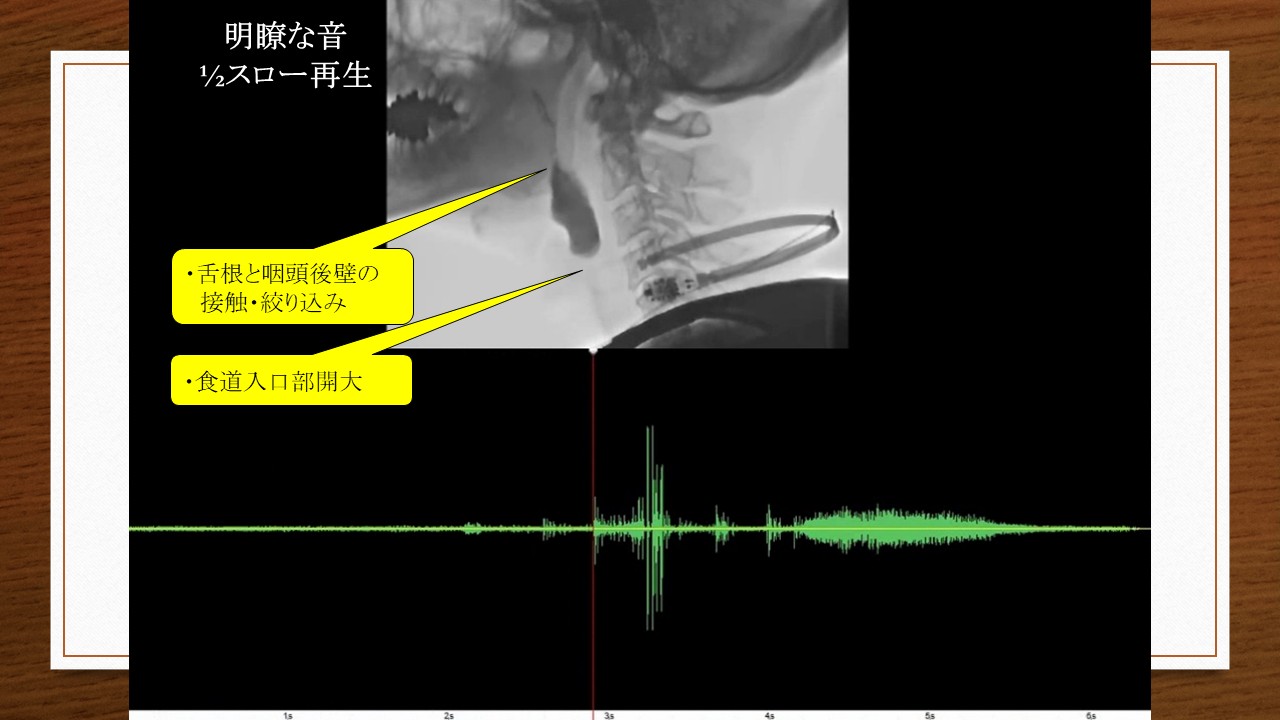

皆さんの職場では嚥下評価を誰がどのように行っていますか?大きな病院では嚥下障害に精通した医師・歯科医師、ベテランの言語聴覚士(ST)、摂食嚥下の認定看護師が中心となり、嚥下造影検査(VF)などで確認しながら行っていることが多いでしょう。しかし、多くの場合はそのような環境が整わないなかで、STや看護師などが水飲みテストやフードテストを頼りに手探りで進めているのが現状ではないでしょうか。

患者さんのQOLに大きく関わる嚥下評価は相当なプレッシャーであり、実のところ、私自身もとても苦手でした。「本当は食べられたんじゃないか」「食形態が合ってなくて誤嚥したんじゃないか」などとよく悩みましたが、それを解決する糸口となったのが「頸部聴診法」です。目で見えない咽頭の嚥下状態を判断できる頸部聴診を活用することで、VFなしでも評価精度を向上させ、自分の評価に自信が持てるようになったのです。

この講座は、「嚥下評価に自信が持てない・・・」「施設でVFができないから不安・・・」「直接訓練に踏み切れない・・・」という現場の声に応えるために企画しています。「頸部聴診法のススメ 前編・後編」で、頸部聴診法の判断基準だけでなく、喉頭触診や咀嚼機能の評価方法など、現場ですぐに使える評価のコツを分かりやすくお伝えします。唾液嚥下の回数やむせの有無に頼るのではない、”嚥下の見える評価“がきっとあなたにもできます!嚥下障害患者さんの”楽食楽座“を実現できるように、嚥下リハビリのスキルアップを一緒に目指しましょう!